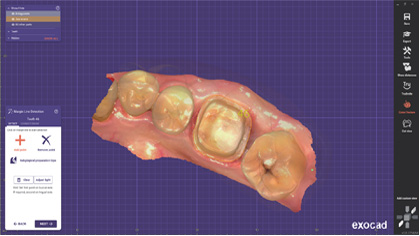

智能掃描

掃描更流暢

軟件智能識別并擯除頰舌側等雜余數據,實時數據干凈清晰無 干擾,口掃更加快速準確。

口掃打印一體化

集成AccuDesign模型編輯工具,支持快速封底、抽殼、加字、排溢孔、智能添加頜架等操作。

支持在椅旁直接打印患者口內數據,輔助醫患達成良好的診療溝通。

支持在椅旁直接打印患者口內數據,輔助醫患達成良好的診療溝通。

廣泛應用 如魚得水

Aoralscan3口內掃描儀,適應癥覆蓋種植、修復、正畸三大領域。無論是椅旁即刻解決方案,還是“診所+技工”聯動解決方案,Aoralscan3都將給您流暢的使用體驗。